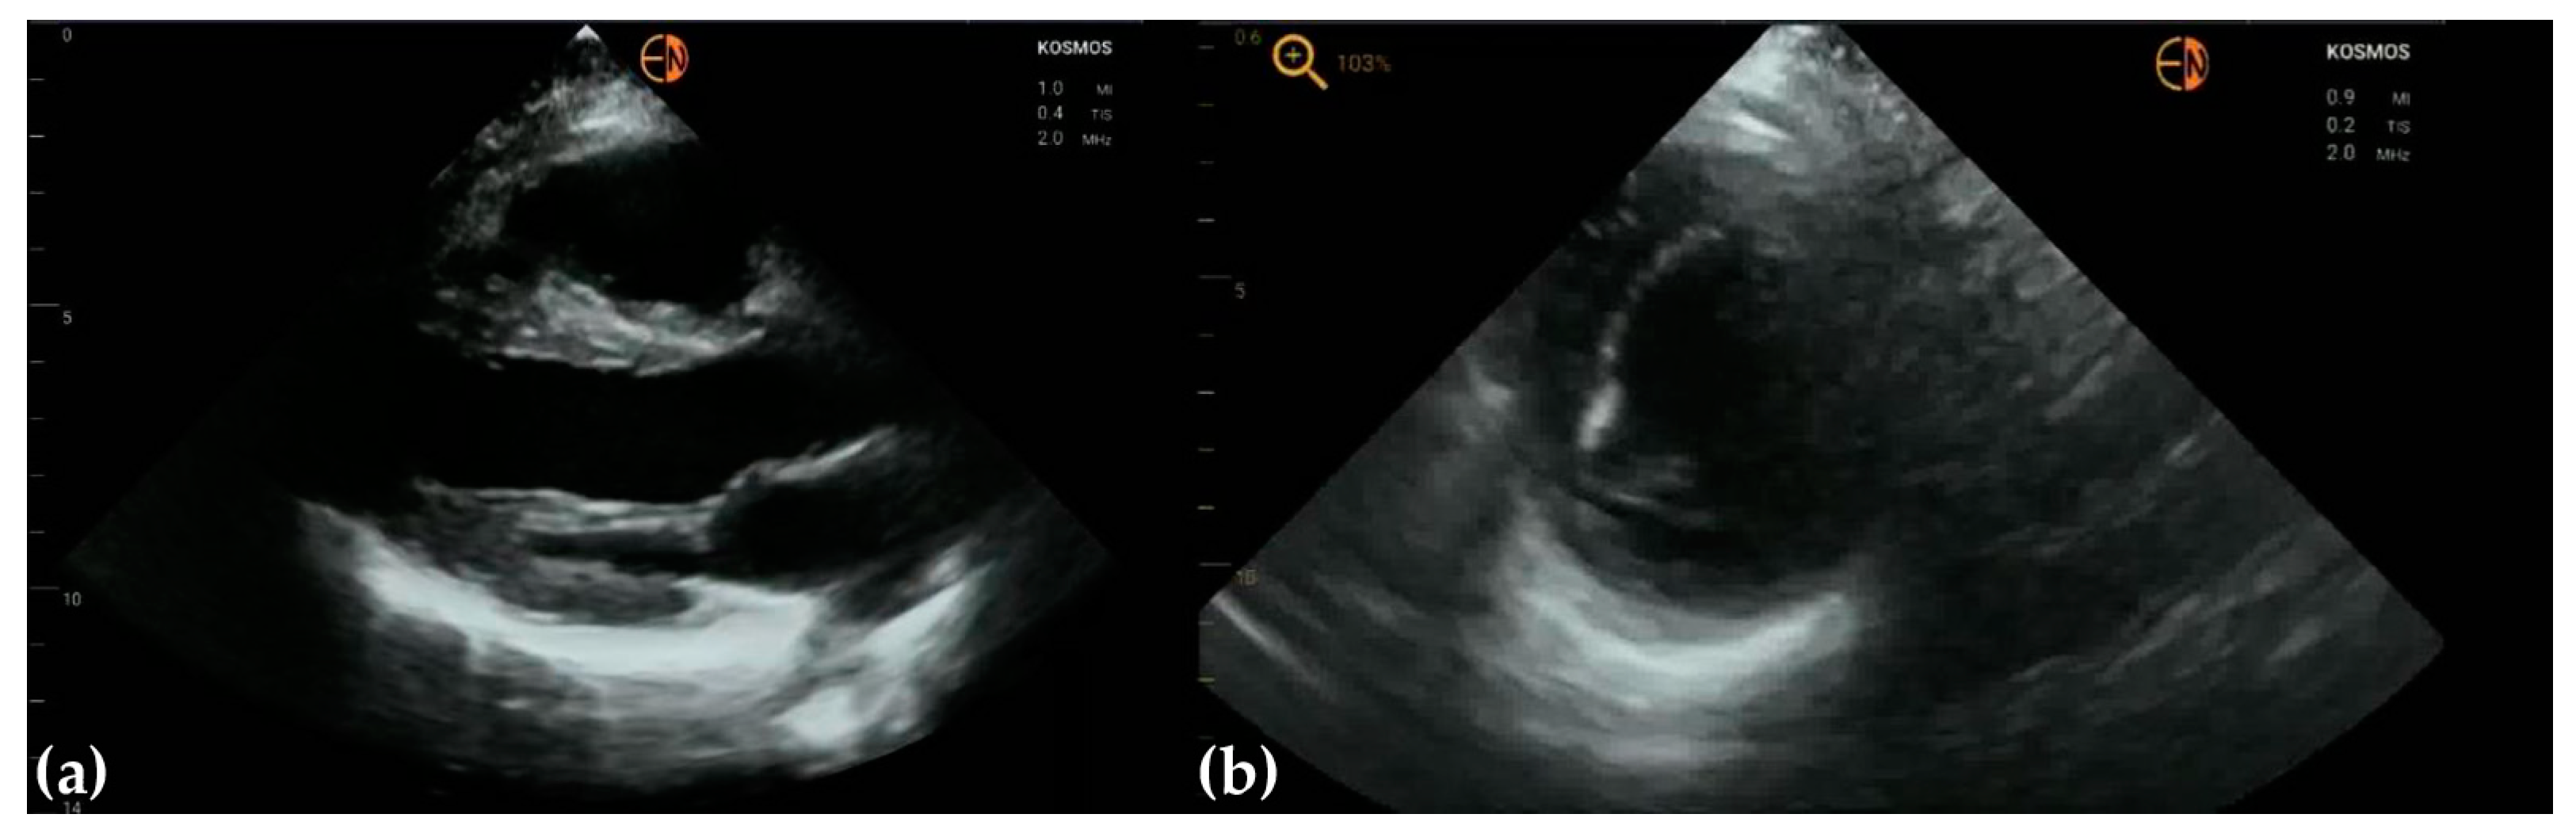

3.4. Other Findings

4. Discussion